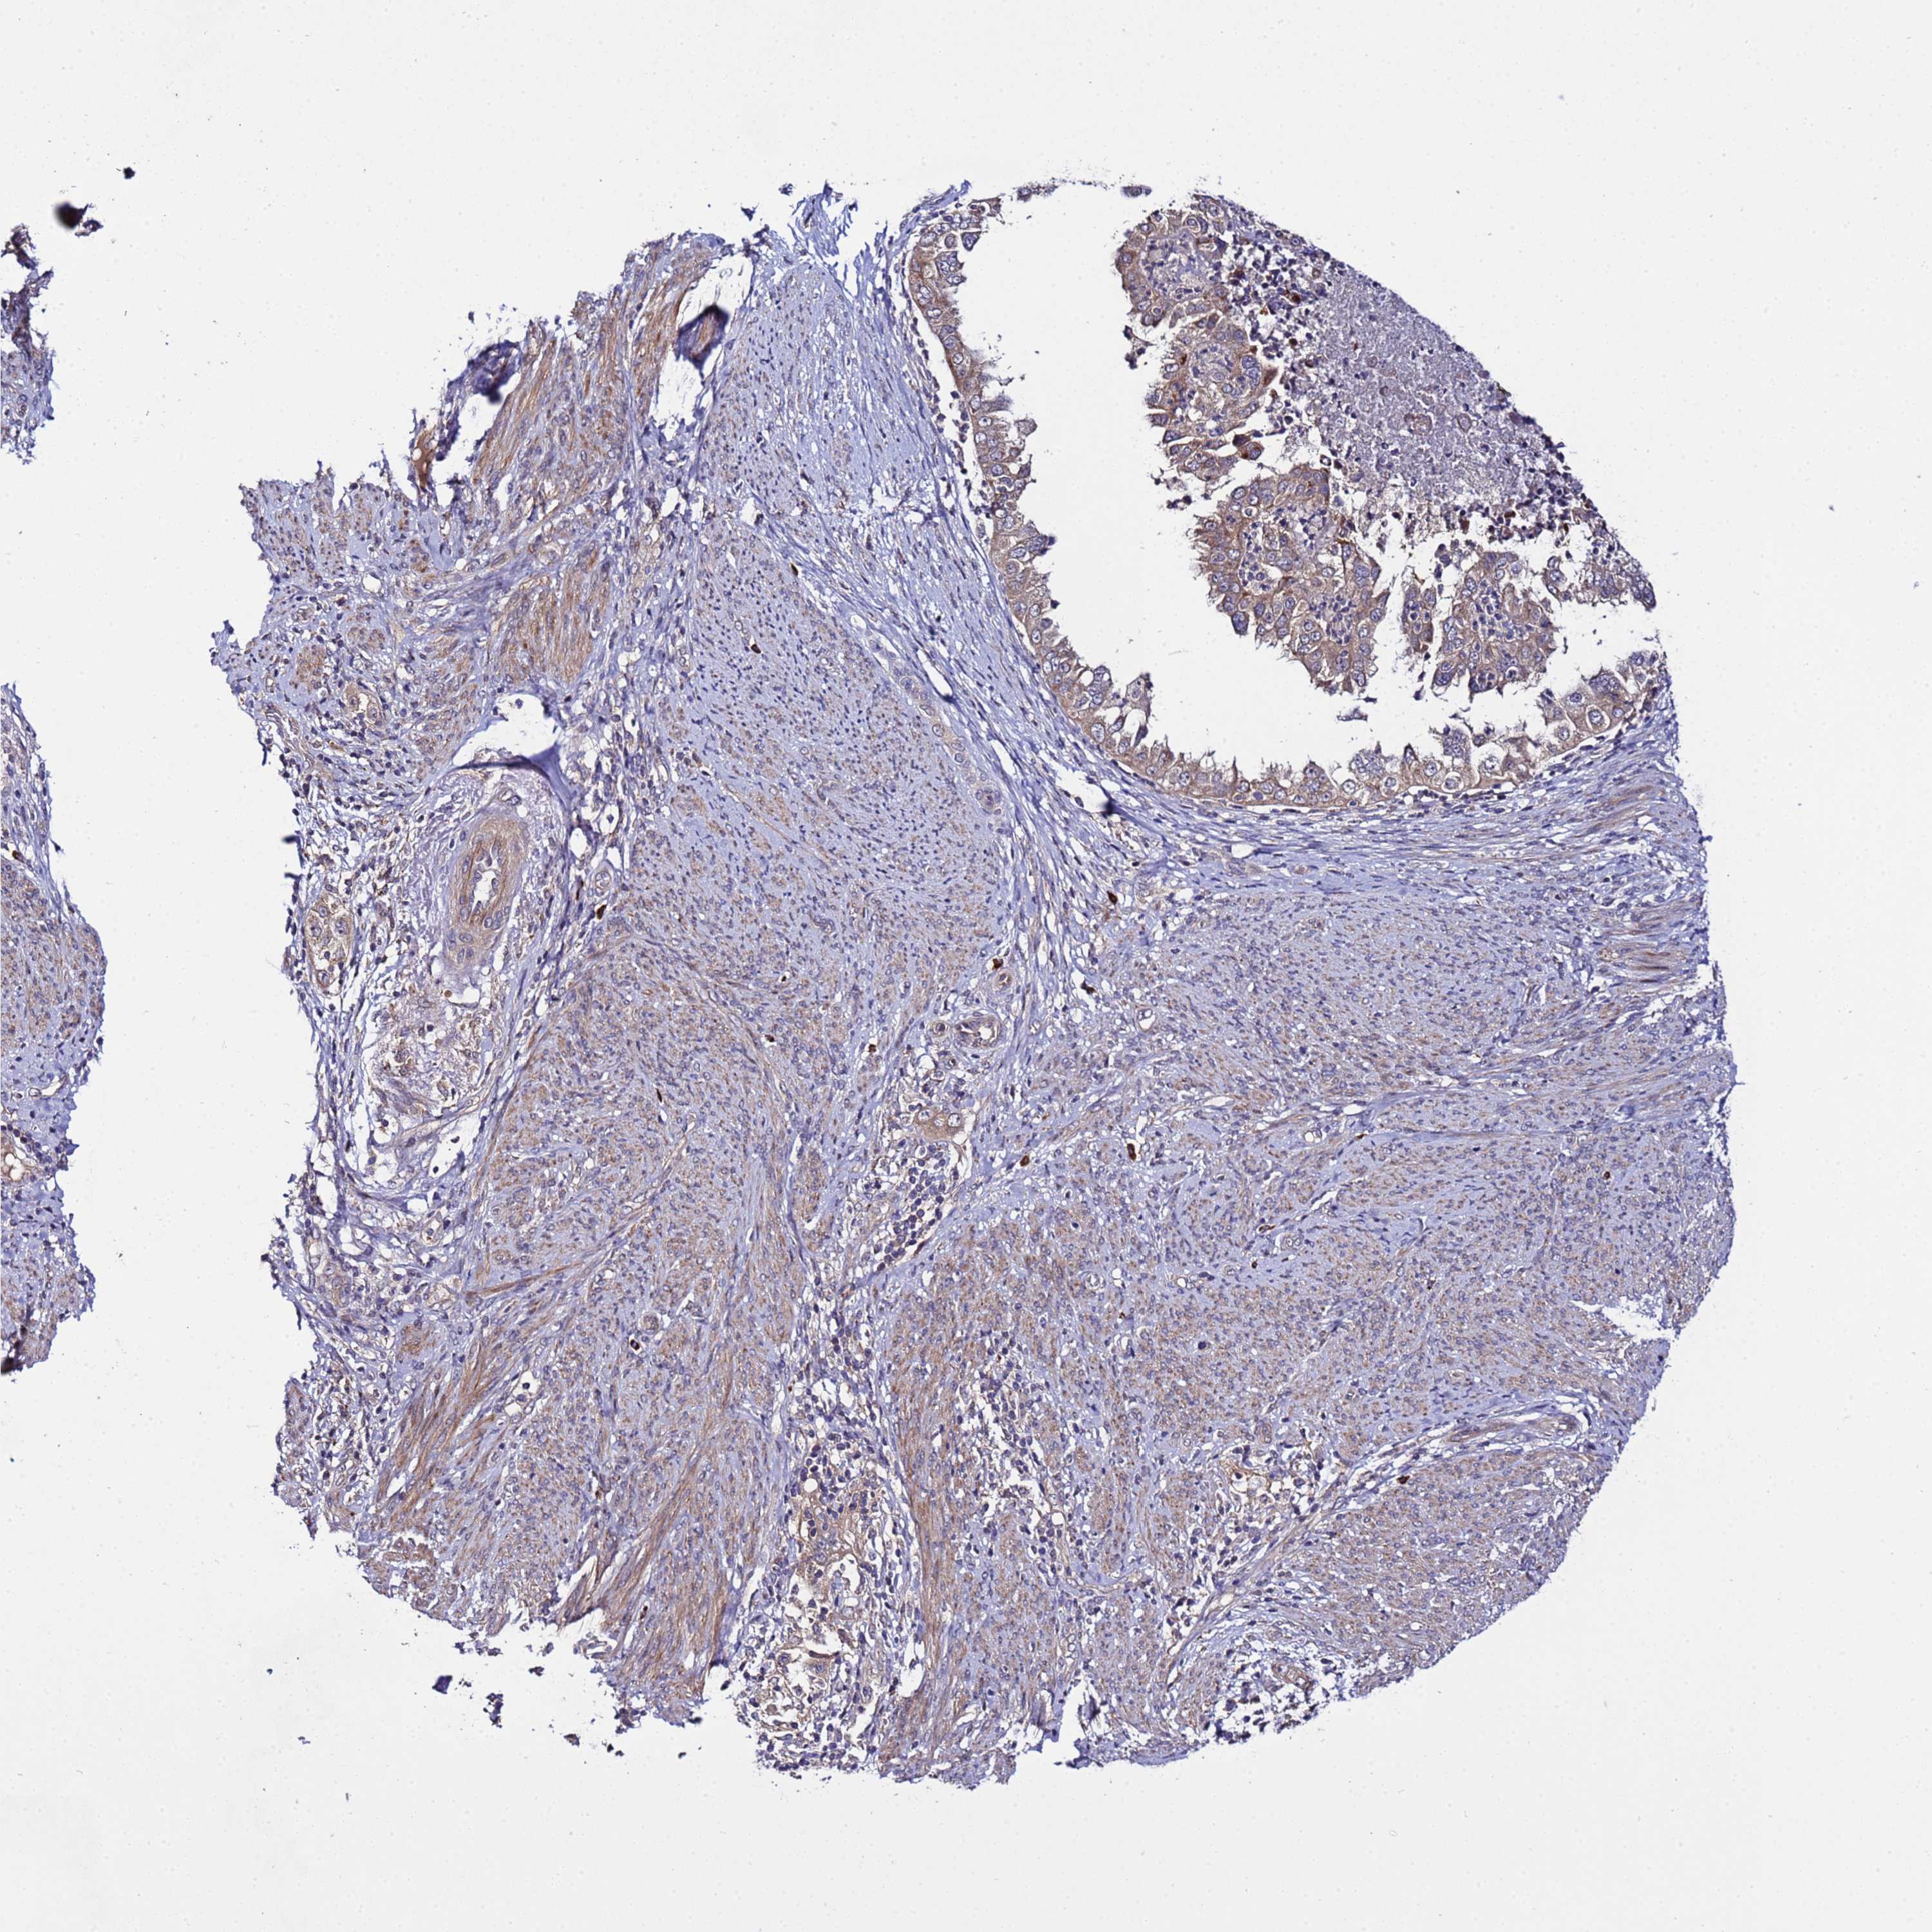

ENDOMETRIAL CANCER - Protein expressioni

A mouse-over function shows sample information and annotation data. Click on an image to view it in a full screen mode. Samples can be filtered based on level of antibody staining by selecting one or several of the following categories: high, medium, low and not detected. The assay and annotation is described here.

Note that samples used for immunohistochemistry by the Human Protein Atlas do not correspond to samples in the TCGA dataset.

Antibody stainingi

Antibody staining in the annotated cell types in the current human tissue is reported as not detected, low, medium, or high, based on conventional immunohistochemistry profiling in selected tissues. This score is based on the combination of the staining intensity and fraction of stained cells.

Each image is clickable and will lead to virtual microscopy that enables deeper exploration of all samples and also displays staining intensity scores, fraction scores and subcellular localization as well as patient and tissue information for each sample.

Antibody HPA017268

Staining

High

Medium

Low

Not detected

Intensity

Strong

Moderate

Weak

Negative

Quantity

>75%

75%-25%

<25%

None

Location

Nuclear

Cytoplasmic/membranous

Cytoplasmic/membranous,nuclear

Adenocarcinoma, NOS